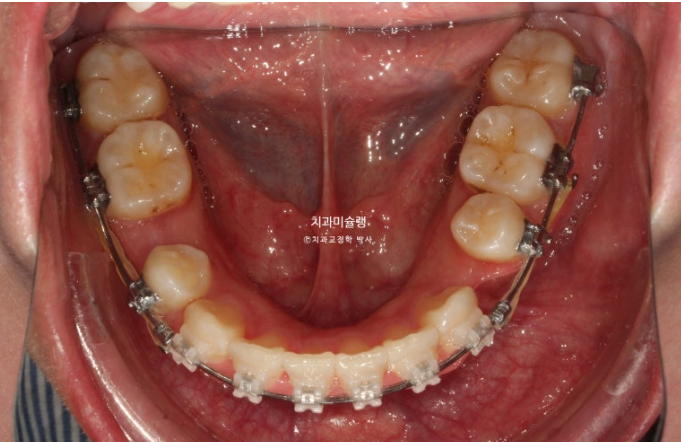

23.08~25.11

옥니, 덧니, 거미스마일, 중심선 이슈, 약간의 돌출이 함께 있는 상황에서 클리피씨로 거미스마일을 어떻게 해결하는 지 봅시다.

2년 전 교정치료를 위해 온 20대 환자분 입니다.

23.08

중심선이 약 2mm 어긋나 있으며 송곳니 덧니가 보입니다.

위 아래 앞니가 깊게 물리는 과개교합도 보입니다.

웃을때 잇몸이 많이 보이는 거미스마일이 있습니다. 특히 위 앞니가 뒤로 쓰러진 옥니 입니다.

작은어금니 하나가 매복되었다시피 깊게 누워있습니다.

치료계획은 누워있는 덧니를 포함해서 작은어금니 4개 발치

단 입이 너무 들어가는 것은 원치 않아 모르페우스 시뮬레이션을 통해 앞니 들어가는 양을 2mm정도로 제한하기로 합니다.

또한 웃을때 잇몸노출량을 줄이고 과개교합 해소를 위해 앞니를 합입하기로 합니다.

클리피씨 교정 선택하셨고 치료에 들어갔습니다.

24.08

치료 후 1년째 사진입니다.

발치공간을 없애는 중입니다.

과개교합 개선을 위해 바이트블럭도 설치하고